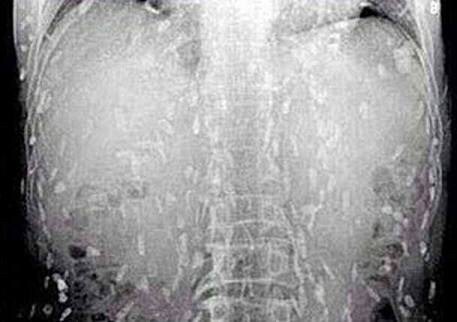

渕崎宇一郎副院長ら消化器内科のグループが、腹部のCT検査を行ったところ、胃壁がただれて肥大化しているのを発見。